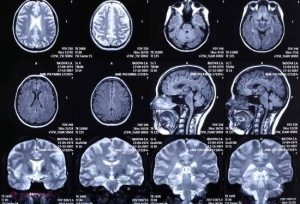

Creierul tău are mai multe sinapse decât stele în galaxie. O bună perioadă de timp, oamenii de știință au estimat că în creierul uman se află aproximativ 100 de miilarde de neuroni. Teoria a fost demontată cu un studiu recent care a presupus punerea uneor creiere într-un belnder și apoi analizarea microscopică a acestora. Cifra rezultată în urma analizei a fost de numai 86 de miliarde de neuroni. Așa că, potrivit teoriei respective, am fi cam o adunătură de idioți.

Dar specialiștii au mers mai departe cu analiza și au obesrvat sinapsele – conexiunile dintre neuroni, care formează o rețea deosebit de complexă. Numărul acestor sinapse este amețitor – 100 de trilioane, spun specialiștii, o cifră de 1000 de ori mai mare decât totalul stelelor care formează galaxia Calea Lactee, scrie antena3.ro.